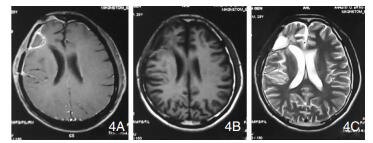

| 图 4 第二次术后MRI |

|